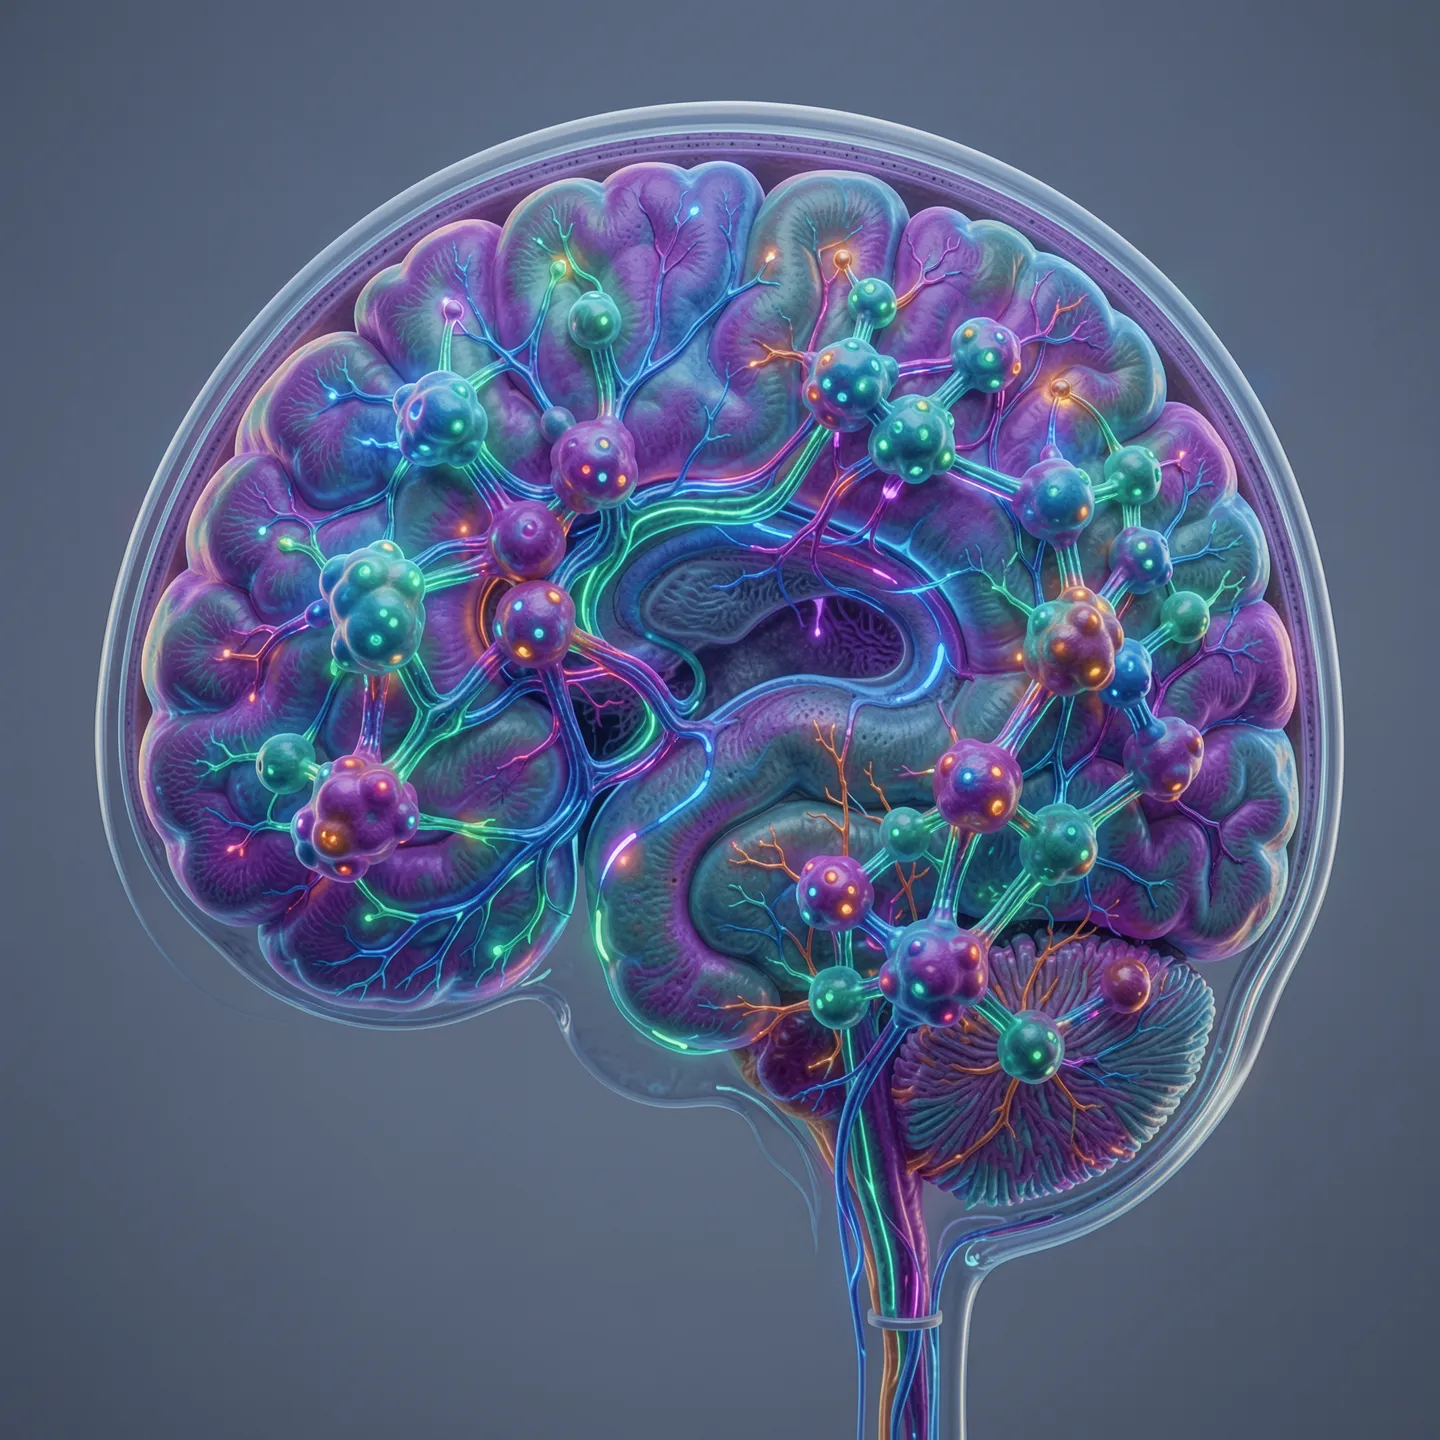

This lesson focuses on the 5-HT2A receptor and its role in cortical activity, neuroplasticity, cognition, and emotional processing. It compares 5-HT2A with 5-HT1A, highlighting the difference between excitatory and inhibitory serotonin effects in the brain. The lesson also explores receptor distribution in cortical and limbic regions, the relationship between serotonin signaling and cognitive flexibility, and how these pathways may influence rumination, attention, mood states, and reward circuits. Clinical links are introduced through discussion of psychedelics, depression models, glutamate activity, and interactions between serotonin and dopamine pathways. Overall, the lesson connects receptor pharmacology with large-scale brain networks and relevant psychiatric symptoms.

- Distribution of 5-HT2A receptors in cortex, limbic system, and related brain areas